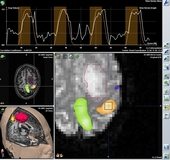

Sistemin hazırlanması 15 dakika sürüyor

Nöronavigasyonun yönteminin çalışma sistemi hakkında bilgi veren Doç. Dr. Tucer, sözlerini şöyle noktaladı: “Operasyon öncesinde hastanın BT veya MR çekimleri yapılıyor. Bir veya daha fazla görüntüleme yöntemi ihtiyaca göre aynı anda kullanılabiliyor. Çekilen bu görüntüler, nöronavigasyonun bilgisayar ünitesine transfer ediliyor. Navigasyon planlama bilgisayarında görüntüler işlendikten sonra ameliyathanedeki üniteye aktarılıyor. Bu görüntüler, sisteme 3 farklı yöntemle tanımlanabiliyor. Yüzeysel belirleyicilerle, anatomik landmarkerlarla veya Z-touch dediğimiz cihazla yüz taraması uygulanarak yapılıyor. Cilt insizyonu ve lezyona uygun merkezli kraniyotomi planlanıyor, nöronavigasyona cerrahi mikroskop ve ultrasound da tanımlanarak cerrahiye başlanıyor. Nöronavigasyon hazırlığı ve planlanması ortalama 15 dakika sürüyor.”